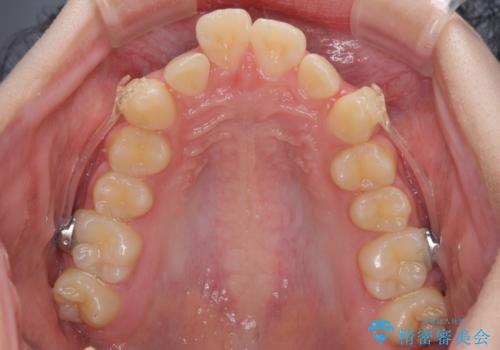

下の前歯が隠れてしまうほど深い咬み合わせ 高校生のインビザライン矯正治療

- 前歯の叢生と深い咬み合わせを気にして来院された患者様です。

奥歯の咬み合わせを見ると、上顎が下顎に対して相対的に前方にありました。

深い咬み合わせを改善するためには、上顎臼歯を後方に移動させつつ、下顎の小臼歯を直立させる必要があります。

インビザライン単体で対応ることも検討できますが、達成する可能性が低いため、カリエールディスタライザーという補助装置を併用して、より確実性を上げることとしました。

奥歯の咬み合わせと深い咬み合わせを改善した後、インビザラインで歯列を整えることとしました。